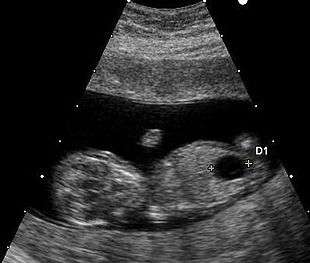

Ultrasound imaging can be used to screen for Down syndrome. Findings that indicate increased risk when seen at 14 to 24 weeks of gestation include a small or no nasal bone, large ventricles, nuchal fold thickness, and an abnormal right subclavian artery, among others.[77] The presence or absence of many markers is more accurate.[77] Increased fetal nuchal translucency (NT) indicates an increased risk of Down syndrome picking up 75–80% of cases and being falsely positive in 6%.[78]